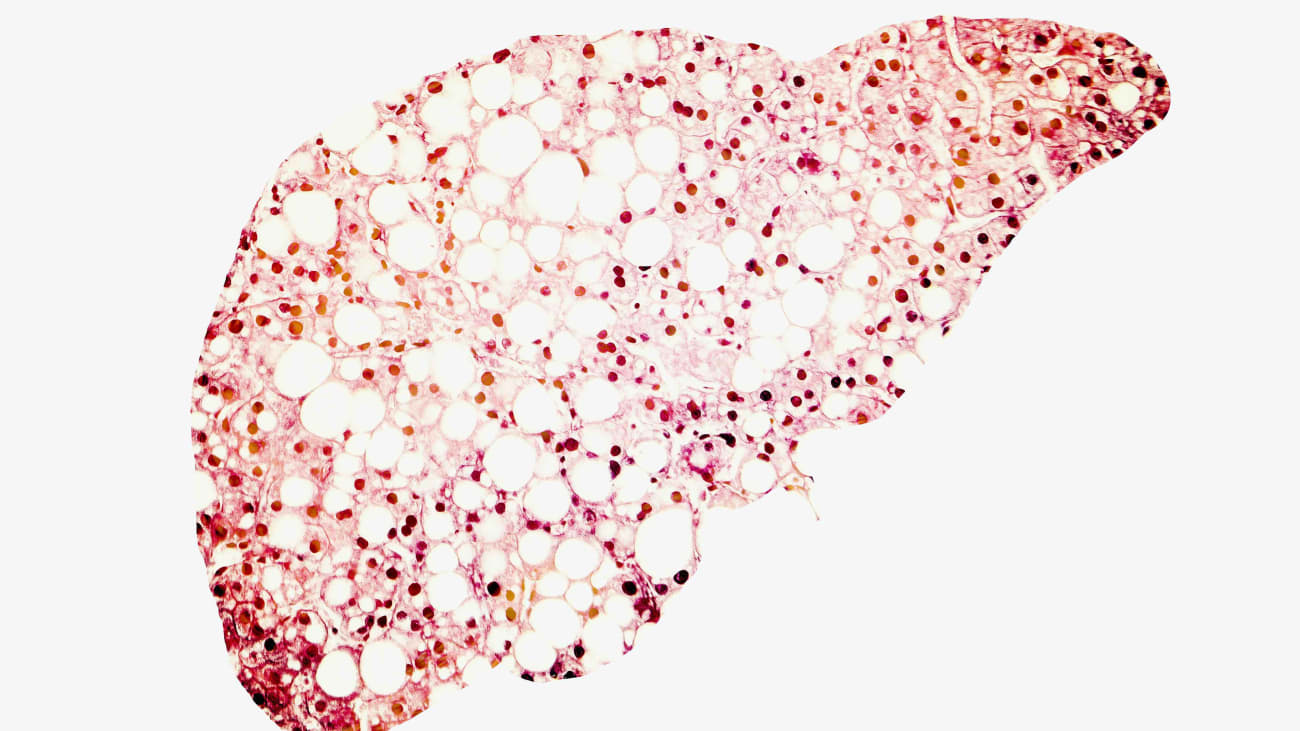

Hi my name is nancy box and I've been tasked with talking to you about cole aesthetic liver diseases. Unfortunately I don't have anything to disclose. So um co static liver disease can involve the bile ducts within the liver and those without on the outside of the liver. And this is not exhausted but um slide. It does show many of the different liver diseases that can cause cola stasis. So anything shown on this slide is fair game for question. However. Um in my experience the majority of the questions are um are based on questions involving PBC and PSC. So this slide comparison contrast the two diseases PBC and PSC. So PBC is a disease that has a predominance in middle aged or perimenopausal women. Um So the majority of patients between the ages of 35 55 years of age upon presentation although there are case reports of teenagers with the disease and patients may record may present as old as their nineties PSC has a slightly increased male predominance. Um And there are two peaks of onset. There are those patients that present in childhood and then the majority who present somewhere between the ages of 20 and 45 years of age in PBC. The target of the attack of the immune system are the interim paddock biliary ducts. While PSC can involve any part of the biliary system, the majority of patients with PB PSC have large or extra paddock biliary duct involvement. Both of these are cole stated cola static liver diseases. So you would expect to see an elevation of the album possibilities and G. T. P. In both of these diseases. Though you can see many auto antibodies and PBC. The hallmark of the disease is the finding of a positive AM A. Which is found in somewhere between 95 98% of patients PSC um can be associated with a variety of positive autoantibodies. But none of these autoantibodies is specific for the diagnosis of PSC. The diagnosis of PBC rests upon the liver biopsy. Um and one should have a normal kel angiogram and PSC. You typically need a kel angiogram which will show the classic features of PSC. Although 15% of patients with PSC have involvement of the interim paddock biliary duct system. Only any auto immune disease can be associated with PBC. Although the majority of patients will complain of sickle syndrome, about 10 to 15% of patients with PVC have thyroid disease as well. The common association of PSC is with inflammatory bowel disease and somewhere between 75 to 80% of patients who have PSC will either have or develop inflammatory bowel disease. The converse isn't true however, because only somewhere between 2.5 to 7.5% of patients who have inflammatory bowel disease will have PSC. The classic symptoms of PBC or fatigue and poor itis. Although um in fact the majority of patients with the disease are asymptomatic although their conversation always involves fatigue and poor itis. Um PSC. Again, most patients are asymptomatic though they can present with pariah itis and if they have features of cholangitis they can have joined us fever and chills. The prevalence of the disease is 40.2 cases per 100,000 in PBC and 6.3 cases per 100,000 in PB PSC. So because it's a board review course the format of my talk is going to be a question and answer um um format. So the first question involves a 68 year old woman who's referred to you for evaluation of elevated liver chemistry's and as you can see the predominant elevation of the alphas and GTP her billy Rubin slightly above the normal range. It's 1.3 she and she has a positive AM a platelet count is 125,000 so it's slightly decreased and she has an elevated I. G. M. Level. What would which of the following recommendation would be the most reasonable to make for this woman A initiate therapy with pregnant alone. Be initiate therapy with her. So dial C. Start her on therapy with a beta colic acid or caliber D. Started on therapy with her. So dial and obey to colic acid or e refer her to a transplant center. So the most reasonable recommendation would be to start her on therapy with ursa dial. And that's because basically when we looked at this lady the diagnosis of PBC has been established with reasonable sensitivity and specificity as such. The S. A. S. L. D. Guidelines suggest that if you have two of the three following criteria you can make a diagnosis of PBC. So if you have biochemical evidence of cola synthesis and the presence of an A. M. A. This should be enough to make the diagnosis of PBC. If you don't have that either of those then you need histological evidence of non supportive destructive cola gingivitis and destruction of interlocutor bile ducts. Um So again the diagnosis of PBC has been established and your saddle is the main story of therapy and PBC. Uh though a bit of colic acid has been FDA approved as a treatment for PBC, it's not recommended as first line therapy. It can be considered as an add on therapy to her. So for patients who have not had a biochemical response with her. So after a year of treatment or for patients deemed to be intolerant diversity, oxy coke acid. Um Though the patient can be referred to a transplant center um If you're not comfortable dealing with the patient, this patient is clearly too early for transplant evaluation. So as you probably recognize, we have the same patients. Um So which of the following variables is not a risk factor for her disease progression in this patient, her age. Remember she's 68 years of age or B. E. You find out that the patients actually a male not female. See that the patient has a liver stiffness greater than 9.6 killer paschal's which is the equivalent of having increased fibrosis D. The patient has a markedly elevated billy Rubin. Or e. The patient has a positive anti glycoprotein to 10 antibody. So the variable that would not be a risk factor for disease progression would be her age. So the risk factors for disease progression and PBC are it tends to be a little bit more aggressive when patients present at a younger age. Male patients tend to have more or more likely to have disease progression as well as patients of hispanic ethnicity. An elevated billy Rubin is considered a negative prognostic marker or um yeah negative prognostic marker as is the presence of G. P. To 10 antibodies and having evidence of advanced fibrosis on a fiber skin is also um suggestive of disease progression. Um Though a little bit controversial most studies seem to suggest that if you have an alkaline foster case greater than 1.5 to 1.67 times the upper limited normal after being treated with one university oxy kulik acid. Um Your prognosis is not quite as good as if you have normalization of your ankle and hospitals. So the same patient which is not recommended by A. S. L. D. Guidelines that should be screened for various is that should be screened for patty cellular carcinoma that you monitor. TSH periodically for direct disease that you give her a statin because this is a pretty wicked looking um lipid panel or e all of the above are recommended for this patient. So the one that the A. S. L. D. D. Guidelines does not necessarily recommend is that statin use must be used in this patient. And that's because although status can be used in patients with PBC and hypercholesterolemia an increased risk of cardiovascular disease has not been firmly established for patients even with this horrible looking lipid profile. Uh While statins are safe and effective in patients with PBC, their use actually needs to be individualized. Taking into consideration other risk factors, screening for viruses is recommended for patients with suspected evidence of cirrhosis. And there were two different studies looking at platelet levels but a reduction in platelet level and or in the last photography score on a fiber scan of greater than 17. Kill A paschal's which is consistent with cirrhosis is also an indication for screening patients for various is patients with suspected cirrhosis should also have regular screening for Battistelli carcinoma. And because thyroid disease can be reported in up to 15% of patients with PBC. It's been recommended that TSH levels also be checked periodically. So we finally have a new patient. So this is a 23 year old male who has undergone a massive for section of the small bowel for Crohn's disease. He's now two months post op and he's been requiring TPN which of the following statement is not true. A is an in that having increased episodes of catheter sepsis increases the likelihood of cola synthesis and liver disease. Be the use of ventral um feedings will increases risk of cola synthesis. See remaining bowel segment less than 50 centimeters increases the risk of cola synthesis. D in the increased duration of TPN use increases the risk of coLA synthesis and liver disease or e life threatening liver disease is rare with TPN induced cola synthesis. So the statement that's not true is that the use of ventral feedings will increase his risk of coal synthesis because in fact it's the opposite it's lack of ventral feedings that can contribute to cola stasis by leading to reduction of gut hormone secretion, reduce bile flow and biliary stasis. So another patient, 52 year old males been diagnosed with ulcerative colitis three years ago and he's really done well and treatment with Miss salome. However, during a recent exam he complains of poor itis and you know that he's yellow. His alphas and GTP are elevated and his billy Rubin. This five he sent viral serology is negative. His a and as positive at 1 to 1 60 a C. A. 19 9 is markedly elevated at 1245. He sent him for a sonogram and that's reported as normal. However you're smart enough to send him for an M. R. C. P. As well. And this shows a stricture you then um schedule him for an ERCP with brushing and a diagnosis of colon carcinoma is made which of the following statements is true about this patient. His lifetime risk of Kalinda carcinoma is 7-15%. Be pancreatic cancer is 14 times greater than the general population. See the risk of colon cancer is 10 times greater than the general population. D screening for colon adenocarcinoma is recommended but it's not terrific. Or e all of the following statements are true. So all of these statements are true. So the important take on message here is that PSC should kind of be viewed as a pre malignant conditions. And although the cost effectiveness of surveillance has not been established it's still recommended. Um There's no sure shot way to screen for colon carcinoma using on the scans or tumor markers. Um And it's important to note that the C. A. 19 9 is not sensitive enough to really rely upon as well as the fact that there are more than 30% of patients who have an elevated C. 19 9 don't have Kalinda carcinoma. It's important to always remember clinically that an ultrasound is operated dependent and it has various limitations. One of which is because it occurs with PSC. Because the PSC can have a sclerotic appearance, ductal dilatation may not always be appreciated on an ultrasound. So this like um slide shows a study that was published about two years ago looking at um the benefits of surveillance. So if you look at the surveillance group they had a significantly higher five year overall survival. And in fact 68% of patients who did have some sort of surveillance had um had a five year survival compared to only 20% who had not had any sort of surveillance. So uh um surveillance significantly lowers the five year old year probability of experiencing a pata biliary cancer related adverse effect events. And again is recommended are, so our next patient is a 48 year old male who's had multiple bouts of pancreatitis. And again he presents with coal, aesthetic liver chemistry's and ability Reuben that's slightly elevated. He has this M. R. C. P. So which additional blood tests might prompt you to recommend treating this patient with predniSONE or toxin Map A. He has a smooth muscle and body. That's 1 to 1 60 B. He has an elevated immunoglobulin G. Four level. See his cereal plasmas low D. He has an elevated I. G. M. Level or e. He has an elevated angiotensin converting enzyme level. So um this question actually has a lot of clues. Probably the most important is that he's had multiple bouts of pancreatitis. But the other thing is that you're thinking of treating him with predniSONE and or toxin map. So this is A. M. R. C. P. That's consistent with some sort of sclerosing cholangitis. So the test you would want to order would be an elevated I. G. G. G. G. G. Four level. So um if you had an elevated serum I. G. Four level this would help make the diagnosis of an I. G. Four sclerosing cholangitis. An elevated serum I. G. Four level is found in somewhere between 66 80% of I. G. Four related disease. The diagnosis of this rare disease can be very difficult to make because the I. G. Four level is neither sensitive nor specific for the disease um In the air cp biopsy is really going to be done. That's gonna be deep enough to be able to stay in for I. G. Four. So it's a difficult way to make the diagnosis. Uh Most patients um have um pancreatic pancreatic involvement. Um and the absence of pancreatitis is rare and i. g44 related cholangitis and in fact 60 to 90% of I. G. Four related sees um present with multi organ involvement is again it's very important to make this diagnosis because it is highly steroid andorra toxin. Retook some apps. Responsive. The next patient is a 19 year old male who is an Ashkenazi jew who's been noted to have significant impact of splenda mentally during a routine exam on careful questioning. He also tells you that he is back pain. His labs show that he is cold static liver chemistry's and he's slightly anemic with a low platelet count. An ultrasound confirms that he is a really large liver and spleen. So you perform a liver biopsy based on this biopsy shown here, the most likely diagnosis would be benign, recurrent interior padded. Coolest Asus or brick Sarcoidosis, Corollas disease, Gaucher's disease or tuberculosis. So the right answer is gosh, she's disease. And this slide shows these Goucher cells which are characterized by like a crinkle tissue paper appearance which has been caused by accumulation of glue grocery, riverside days and cook for cells and macrophages. Um these um these cells can infiltrate the liver spleen and bone marrow. Um about 94% of patients with gashes will also have bone marrow involvement. And again, there are several clues to making the diagnosis of Galaxies disease, including the fact that this patient is an Ashkenazi jew, he's got back pain and he may have some bone marrow involvement. So um the um the key points here that attaches disease is the most common license almost storage disease and is caused by deficiency of glucose, cerebral side is this is a picture of tuberculosis where we see Casey and granulomas. Um and one would expect could possibly see a positive afb stain. The next one um slide shows non Casey and granulomas. And one would expect to see that in sarcoidosis. Brick is characterized by recurrent episodes of cola static joined us. Um The histology can show central lobby like cola stasis. However, typically you don't see evidence of progressive liver disease and or other features of obstruction and lost of all this is corollas disease, which is a rare inherited disease characterized by dilatation of the interim Paddick bile ducts. So the next patient is a 26 year old male who has a history of ulcerative colitis. And he's undergone a living donor liver transplant about three months ago for PSC. He now presents to the emergency room with politis and low grade temps. His donors C. M. V. Positive and he C. M. V. Positive. So the CMB matches his laboratory tests showed. Um That is billy Rubin is now 4.8 and he's cola static liver chemistry's his attacker lima's um three months out as eight nanograms per mil leader. And he has an ultrasound which shows no ductal dilatation. Um And although his he has a Peyton hepatic artery, there is some high resistance. Um Doppler wave forms reported, which are the following would be the most likely diagnosis based on what we have here, would it be the patient has recurrent PSC. You suspect in a systematic biliary stricture. See acute cellular rejection. D. The patient has C. M. V. Hepatitis or E. Um He's having a flare of all sort of colitis. So this question is loaded with clues. Again, his patient, it's a living donor liver transplant. The timing is three months after the transplant. His tackle LIMAs is actually good for um someone three months after transplant. And the big clue or hint here is that he's got these high resistance. Doppler wave forms. So the right answer would be that you suspect that he has an N. S. Thematic biliary stricture. So although C. M. V. Infections are more common in the first months after transplant, patients with C. M. V. Hepatitis typically are sicker and it's usually seen when you have a C. M. V. Donor um with the C. M. V. Negative recipient. And if you recall both of these, the donor and the recipient with CMB positive, acute cellular rejection always remains a possibility. Um And a liver biopsy may in fact be indicated. However the patient does have good tackler lima's trough levels. Um The current PSC occurs in 20% of PSC transplant so it's important to always look for occurrence. However the median occurrences usually 4 to 5 years and so this would probably be a little bit early for disease recurrence. Living donor transplants are known to have a higher rate of biliary complications than disease donor transplants. Making you think maybe there's a biliary complication and based on the Doppler studies which show increased resistance in the paddock artery um You may have a paddock artery stenosis that can predispose to biliary complications due to ischemic injury. Um You have to remember that the paddock arteries, the primary supply of the bile ducts. So the next study in this patient would be a clan a clan diagram to exclude a biliary stricture. Uh So our next patient is a 43 year old male who has altered a colitis and he presents with new onset of Jaundice. Kalla static liver chemistry's and he's got a billy Rubin of 6.8. He has an M. R. C. P. And it shows a dominant structure. Which of the following statement is not true or false. Which which is false. A. A dominant stricture occurs in 45 to 58% of patients. Um With this presentation 80% of patients with PSC. Have I. B. D. C. 30% of patients with IBD have PSC. Um D this patient should have an ERCP with brushing or e. There's no medical therapy that's been approved of this particular disease. So the statements that that is not true is that 30% of patients with I. B. D. Do not have PSC. And if you were awake at the beginning of the talk you would have noted that. Um Because while 80% of PSP PSC patients have IBD, it's only somewhere between two and 8% of patients with IBD who have PSC. A colonoscopy with biopsy should be performed in all newly diagnosed with PSC. Even if they're asymptomatic because of this highest high likelihood of association with inflammatory bowel disease. Um If the dominant structures seen it should be brushed um and biopsied. And if Qala ange itis occurs in a patient with dominant structure. They should have a correction of the bio duct obstruction along with antimicrobial therapy. The risk of colorectal cancer increases in patients with us cm PSC. And surveillance column colonoscopies are usually recommended at 1 to 2 year intervals and patients that are the U. S. C. And P. S. C. And it's also been recommended that ultrasound surveillance for gold bladder polyps um be performed because of the increased um risk of gold bladder cancer. This is a histology question. So which liver biopsy would match the following patient, A 52 year old woman who's got cola static liver chemistry's Zampa Lehman examples machine here and the positive AM A. A. B. C. D. Or E. And the right answer would be that this is a patient with PBC. So you need to recognize that this is a bile duct and put in a portal track. There's mixed inflammatory infiltrates which are attacking or disrupting the basal membrane of this sick looking bile duct. And this is a classic stage one PBC lesion. So this picture was interest had a kalandia carcinoma. And you see um glands lined by cells and there's an increased nuclear um nuclear solar um cytoplasmic ratio with prominent new clio lie this is a picture of PSC which if you're lucky enough to see on a biopsy is very helpful in making diagnosis of PSC. Where you see this onion. Skin fibrosis. Um The fact that this patient had a positive AM A. Is not consistent with PSC. So again this is not the right answer. Um The next picture is a patient comes from a patient automatic amyloidosis and you'd use a congo red stain to confirm that diagnosis. A pearl that's been thrown around for years is that you should be very cautious when you buy if you intend on bypassing someone who has suspected amyloidosis because of the risk of aesthetic rupture and bleeding. And the last picture comes from a patient, a biliary atresia, which is the most common cause of neonatal cola synthesis um where you can have partial of complete obstruction of the common bile duct. So this is my last question and I'm gonna do it as a jeopardy question. So I'm going to give you the answer and pretend I'm Alex Trebek. And you're gonna give me the question. So the answer is a genetic disease caused by a mutation and the A. B. C. B. 11 gene that leads to a deficiency of the BCF protein and has an increased risk of patty cellular carcinoma in some individuals. So the question is what is benign recurrent inter paddock? Cold synthesis one of brick one. Brick to progressive familial inter paddock. Coolest Asus one or P 51. Um What is perfect to e what is P. 53? And the question is what is progressive familial interim paddock um cold synthesis to so um that completes my talk. Good luck. Bye bye